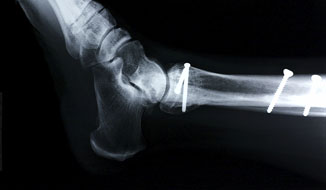

hip fracture